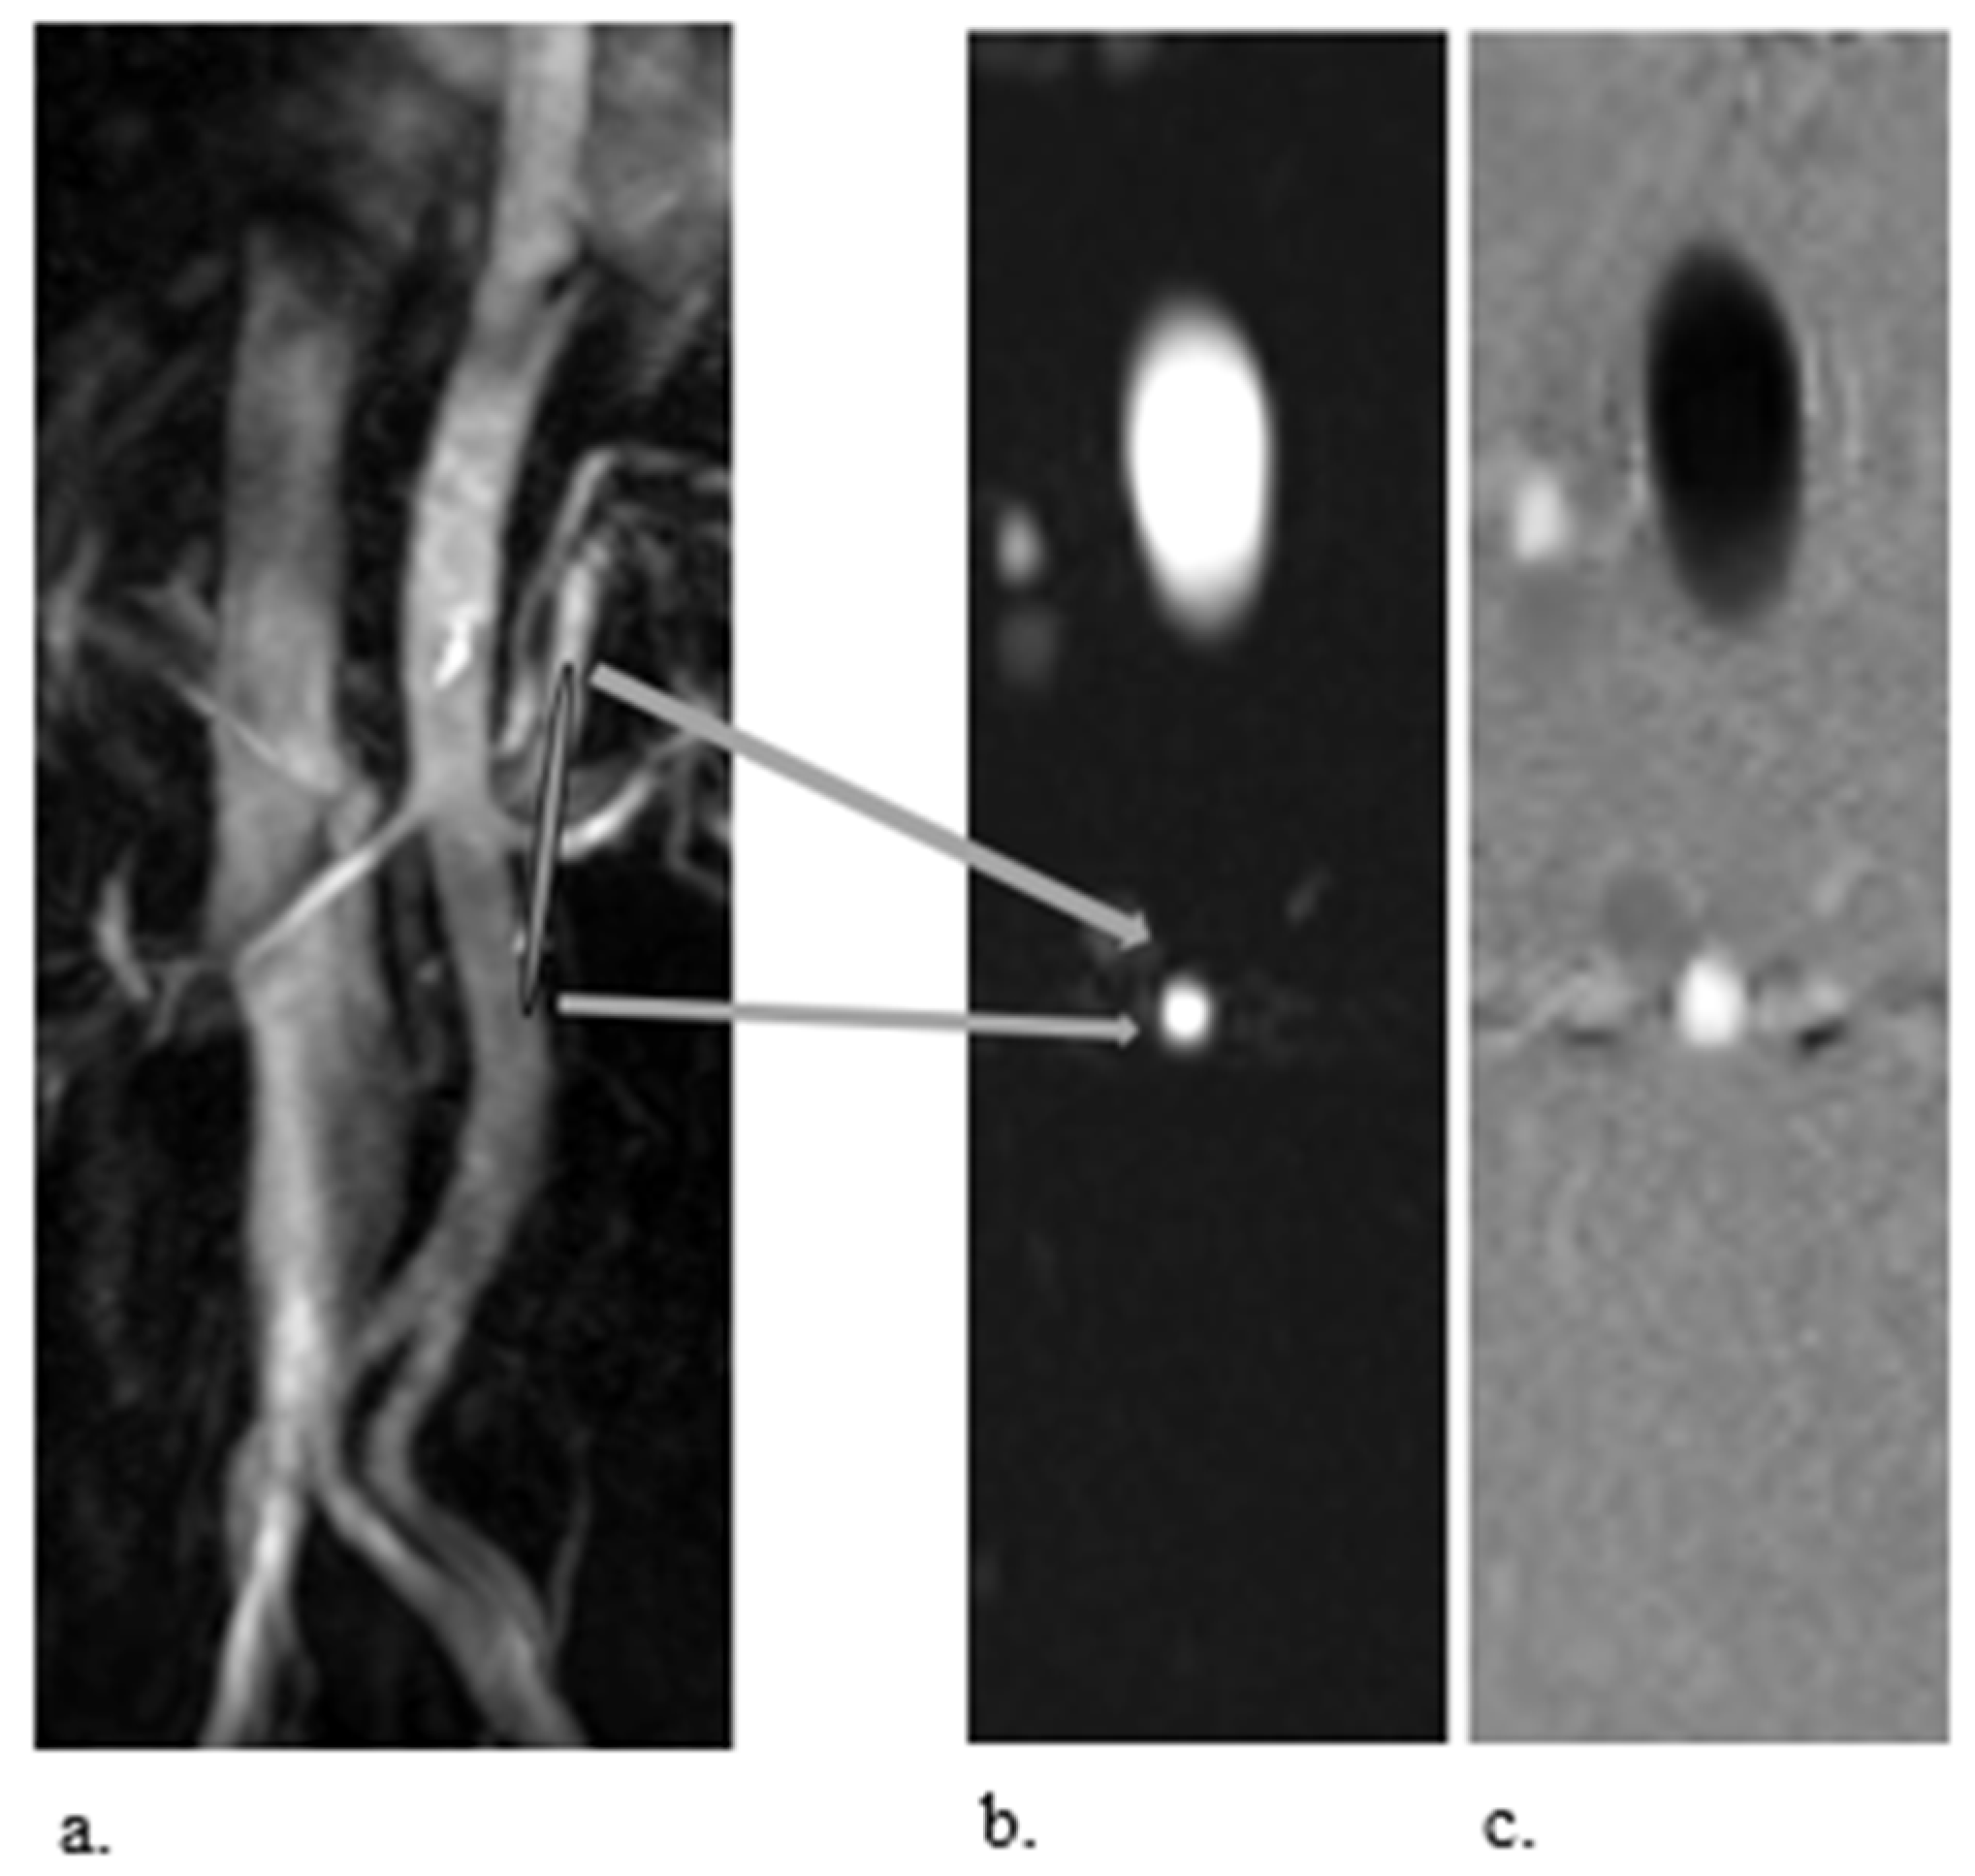

Figure 2. Example of phase–contrast MRI of the left renal artery in a 35-year-old healthy man. (a) Shown is a maximum-intensity projection of the entire aorta, used to localise the left renal artery (halfway along the bar). In order to obtain accurate velocities, an exact orthogonal plane of the vessel has to be selected; (b,c) show the resulting images of respectively the magnitude of the signal (b) and the velocities (c) of the left renal artery in a sagittal oblique plane. Post-processing allows quantification of the blood velocity in the vessel by placing ROIs in the lumen of the artery.